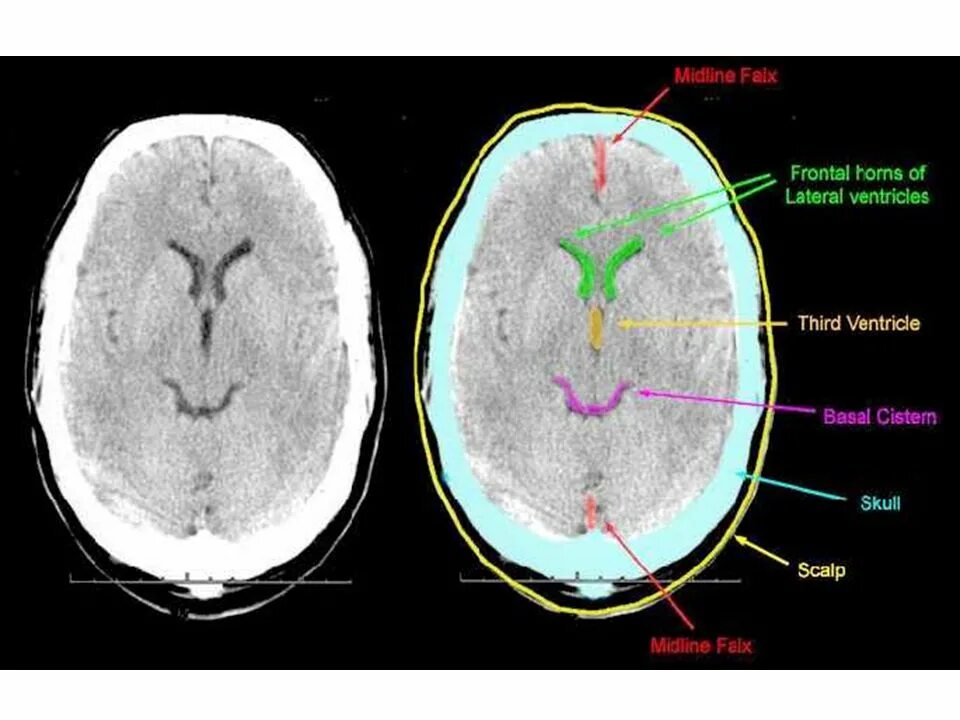

Цистерны на кт